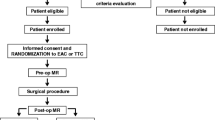

This was a prospective, observational; single-center clinical trial was carried out at the Clinical Department of Anesthesiology and Perioperative Intensive Therapy, Division of Cardiovascular Anaesthesia and Intensive therapy, and Clinical Department of Cardiovascular Surgery at the University Medical Centre in Ljubljana (Slovenia), between March, 2016 and December, 2018. Approval for the trial was obtained from the National Medical Ethics Committee (Affiliation: Ministry of Health of Republic of Slovenia; approval number: 22 k/04/15) and a written informed consent was obtained from each patient before enrolment into the study. The trial was conducted in accordance with the Helsinki Declaration and registered at ClinicalTrials.gov (NCT02697786) before patient recruitment was started.

Power of study calculation was based on the assumption that the absolute number of MES would be around 100/procedure (SD ± 25 MES) [12] and any change in the mean difference of 20 MES/procedure or greater would suffice as a clinically relevant effect for a two-sided test. To achieve 80% statistical power with a significance level (α) of 5%, the ClinCalc sample size calculator (clincalc.com/stats/samplesize.aspx) defined our need as 25 patients per group, indicating a total of 50 patients across the two treatment groups. Considering an estimated 10% drop-out rate due to a poor trans-temporal window for transcranial Doppler (TCD), 60 patients were recruited to avoid risk of low power.

Inclusion criteria

Patients> 18-years-old, II or III class according American Society of Anesthesiology (ASA) classification, diagnosed with isolated severe high-gradient aortic stenosis according to ESC/EACTS 2017 guidelines (AVA less than 1.0 cm2, mean gradient>_40 mmHg and indexed aortic valve area less than 0,6 cm2/m), who were referred to Clinical Department of Cardiovascular Surgery at the University Medical Centre in Ljubljana for mini-AVR, were eligible for recruitment.

Exclusion criteria

Patients with a poor acoustic window, epilepsy, psychiatric illness, carotid pathology, pathology of coronary arteries, brain stroke and alcohol abuse were excluded from the study.